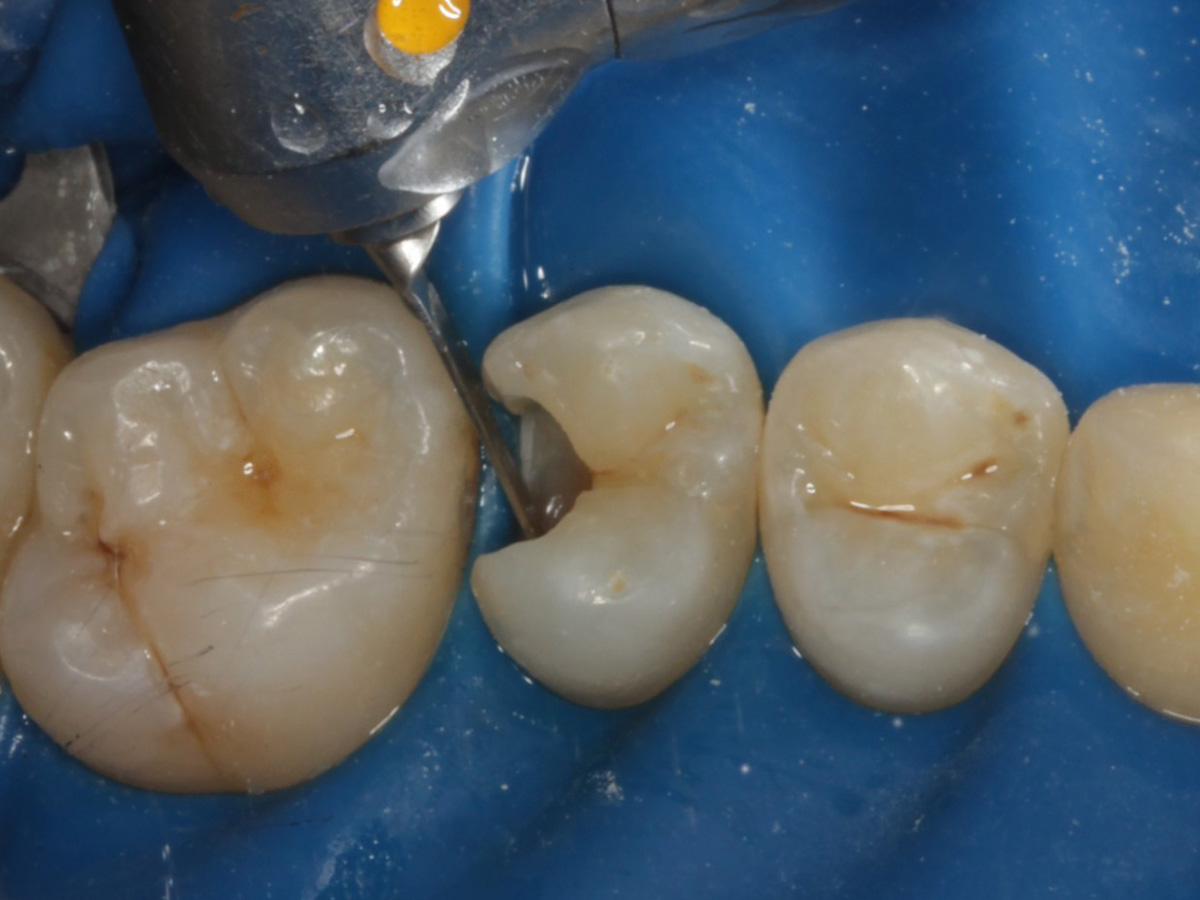

Abbildung 5

Defektdarstellung

Abbildung 6

Kariesexcavation pulpennah mit Kunststoffrosenbohrer